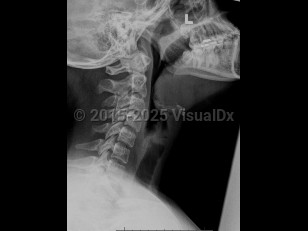

Epiglottitis

Epiglottitis is a potentially life-threatening inflammation of the epiglottis and supraglottic space caused by infection (eg, Haemophilus influenzae type b [Hib]) or injury (eg, foreign body, caustic substance, thermal damage). As the epiglottis swells, it can cause airway obstruction and create a medical emergency. Presenting symptoms include high fever, sore throat, difficulty swallowing, dyspnea, hoarseness, stridor, tachycardia, drooling, and hot potato voice or dysphonia.